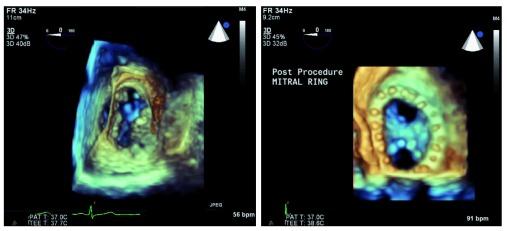

Introduced in 1977, transesophageal echocardiography (TEE) offered imaging through a new acoustic window sitting directly behind the heart, allowing improved evaluation of many cardiac conditions. Shortly thereafter, TEE was applied to the intraoperative environment, as investigators quickly recognized that continuous cardiac evaluation and monitoring during surgery, particularly cardiac operations, were now possible. Among the many applications for perioperative TEE, this review will focus on four recent advances: three-dimensional TEE imaging, continuous TEE monitoring in the intensive care unit, strain imaging, and assessment of diastolic ventricular function.

经食管超声心动图(TEE)于1977年问世,它通过心脏正后方的一个新声学窗口进行成像,从而能够更好地评估多种心脏疾病。此后不久,TEE就被应用于术中环境,因为研究人员很快意识到,现在在手术期间,尤其是心脏手术期间进行连续的心脏评估和监测成为了可能。在围手术期TEE的众多应用中,本综述将聚焦于四项最新进展:三维TEE成像、重症监护病房中的连续TEE监测、应变成像以及舒张期心室功能评估。